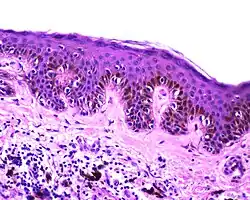

Dysplastic nevus Usually a compound nevus with cellular and architectural dysplasia. Like typical moles, dysplastic nevi can be flat or raised. While they vary in size, dysplastic nevi are typically larger than normal moles and tend to have irregular borders and irregular coloration. Hence, they resemble melanoma, appear worrisome, and are often removed to clarify the diagnosis. Dysplastic nevi are markers of risk when they are numerous, such as in people with dysplastic nevus syndrome. According to the National Institute of Health (NIH), doctors believe that, when part of a series or syndrome of multiple moles, dysplastic nevi are more likely than ordinary moles to develop into the most virulent type of skin cancer called melanoma.[19]

Characteristic rete ridge bridging, shouldering, and lamellar fibrosis. H&E stain.